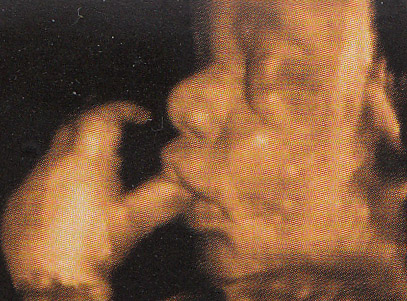

3D/4D Ultraschall